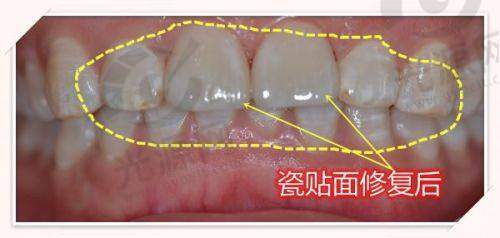

他主要擅长复杂种植、微创前牙美学修复、牙体牙髓病治疗、牙周基础治疗、复杂烤瓷冠桥修复、活动义齿修复、全口义齿修复项目等。他在鼎植口腔九福门诊部为患者提供着高质量的口腔诊疗服务。

她在全口/半口即刻种植、即刻修复、复杂种植、根管治疗、前牙美学相关复杂病例的系统性治疗方面有着深厚的造诣。她凭借专精的知识和贴心的服务,赢得了患者的信任和好评。